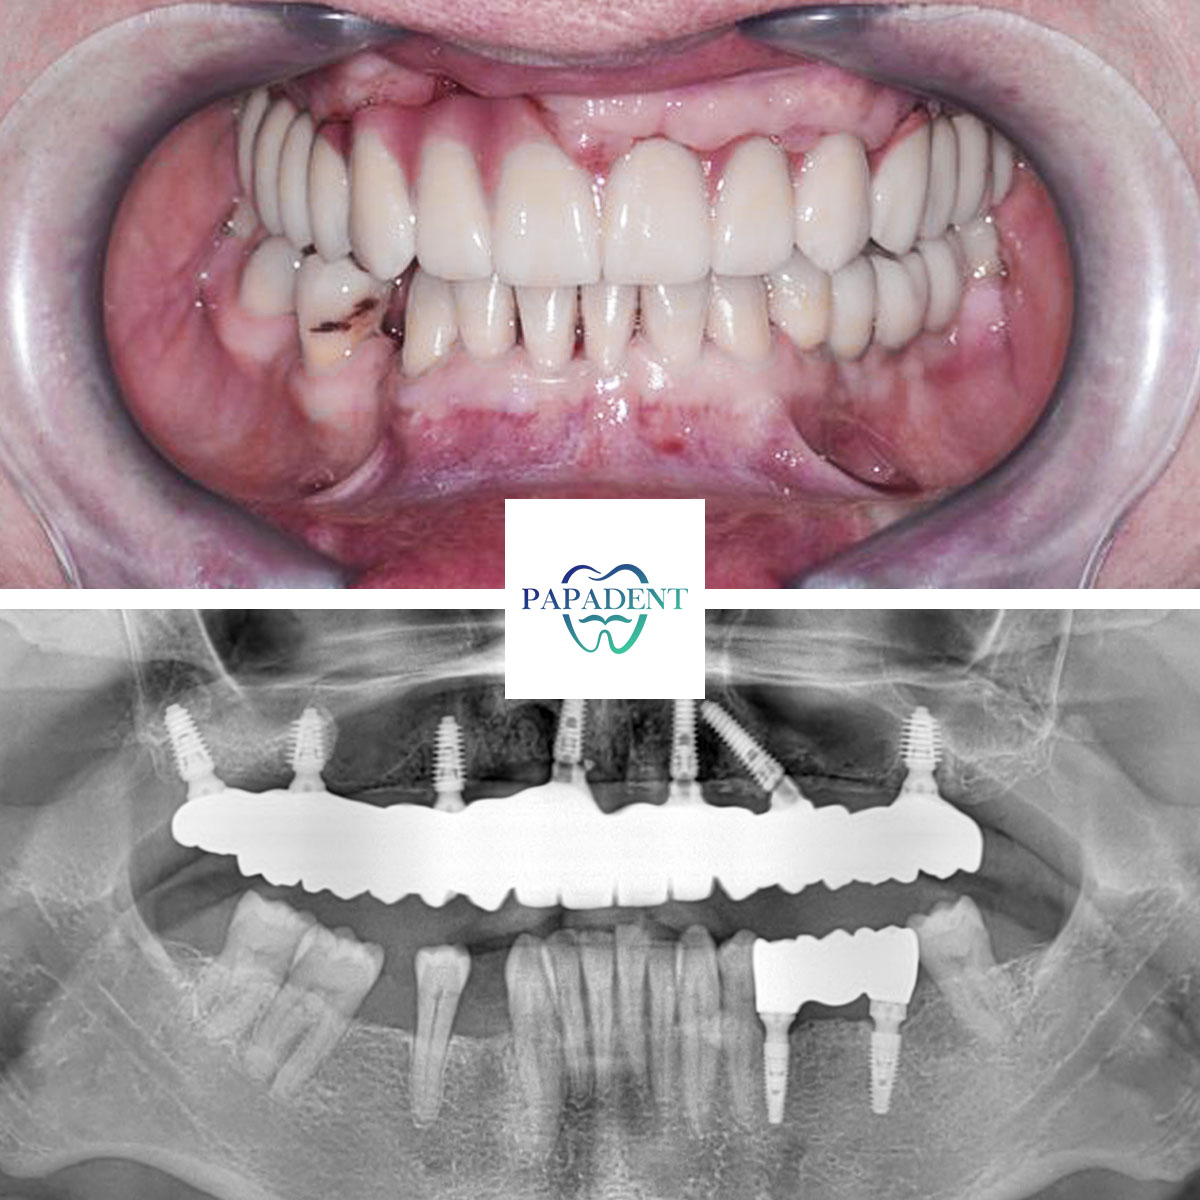

Trūko dalies viršutinių dantų, dalis likusių aptrupėję, praradę natūralią spalvą, todėl „PAPADENT“ specialistai pasiūlė juos pašalinti. Nejautroje ištraukus dantis, įsriegti implantai ir pritaikytas viso žandikaulio protezas net su 7 implantais!

Aktyvūs sportininkai dažnai susiduria su įvairiomis kūno traumomis, tarp jų ir dantų pažeidimais. Tokiais atvejais, kai dėl nelaimingų atsitikimų ar per didelio fizinio krūvio dantys būna pažeisti, svarbu pasirinkti tinkamą gydymo sprendimą. Pavyzdžiui, kikboksininkui, dėl ilgų metų praleistų ringe, trūko dalies viršutinių dantų, o likę buvo aptrupėję ir praradę natūralią spalvą. Tokiu atveju, „PAPADENT“ odontologijos klinikoje Vilniuje buvo rekomenduota pašalinti pažeistus dantis ir įsriegti implantus, po kurių buvo pritaikytas viso žandikaulio protezas su net 7 implantais.